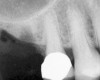

After penetration into the sinus is achieved, a sterile amalgam carrier is used two times to deliver a radiopaque bone substitute into the osteotomy. Then the osteotome used to infracture the subantral floor is lubricated with saline and inserted into the osteotomy until the stop on the osteotome reaches the alveolar crest. This pushes the bone substitute up under the sinus membrane and elevates it. Two more carriers of bone substitute are delivered in the same manner. This will provide around 2 mm of bone height in the sinus (four carriers provide around 2 mm of bone height). A radiograph is then taken to verify that the membrane was elevated, and the bone graft should appear as a dome (Figure 4). If the sinus floor has not been penetrated despite the impression that it was, the bone-graft material may have been pushed laterally. If this occurs, there will be no dome on the radiograph, but, rather, increased osseous density on the lateral aspect of the osteotomy. If this occurs the osteotomy needs to be deepened.

Figure 4  After infracturing the subantral wall with a 3.5-mm osteotome, bone was added and the presence of a dome was confirmed with a radiograph.

Figure 4